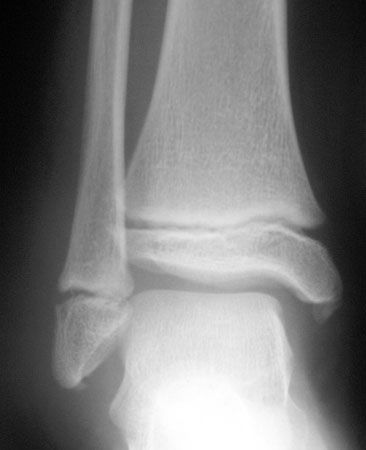

Pédagogie Les fractures de cheville chez l'enfant , M.C. Maximin Hôpital Privé La Résidence du Parc, 13010 Marseille - N°142 - Mars 2005 ● 27 min de lecture